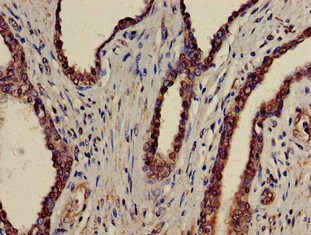

IHC (Immunohiostchemistry)

(The image on the left is immunohistochemistry of paraffin-embedded Human esophagus cancer tissue using ATAD1 Antibody at dilution 1/100, on the right is treated with fusion protein. (Original magnification: x200))